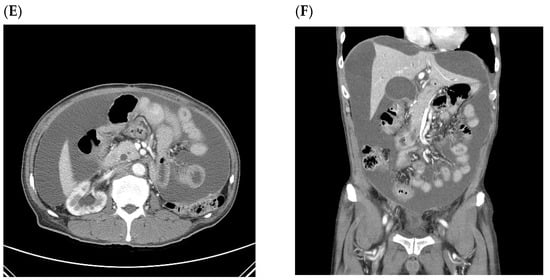

| A patient who first recurred with malignant ascites without other CT findings related to peritoneal seeding (later confirmed by cytology) (n = 1) | ||||||||

| Pt 9 | 49/F | TG | T3N3a | small pelvic cavity | ||||